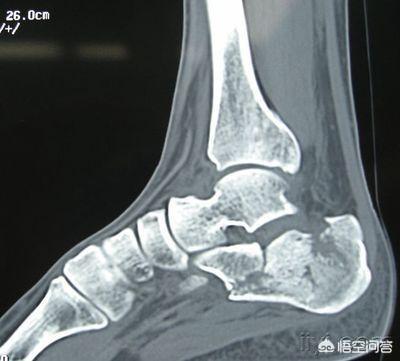

左脚跟粉碎性骨折手术后引流管流血正常吗?

跟骨是一“皮包骨”的骨头,发生骨折后手术治疗的一个严重的并发症就是皮肤坏死,皮肤坏死很大的原因之一就是皮肤软组织和跟骨表面之间有间隙,淤血可以填充这个间隙,把皮肤和骨表面隔开,皮肤软组织和骨骼相互依存,唇亡齿寒,它们被淤血隔开,容易引起感染和皮肤软组织,甚至骨骼的坏死。

医生在伤口放置引流管,就是怕伤口里积血太多,引流管可以把伤口里的淤血放出来,让皮肤软组织和骨面紧贴,形成一整体,减少组织坏死的几率,减少感染,有利于跟骨的生长,更有利于消肿。